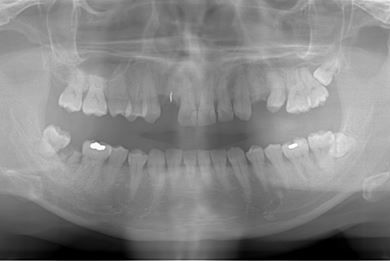

| 性別/年齢 | 男性 / 36歳 | ||||||||||||||||||||||||||||||||

| 主訴 | 歯が折れているので、インプラントにしたい。 | ||||||||||||||||||||||||||||||||

| 治療方針 | 抜歯と同時にインプラント埋入を行い、治療期間を短縮する。 | ||||||||||||||||||||||||||||||||

| 治療内容 | インプラント2本(抜歯即日インプラント治療)、ジルコニアフレームオールセラミッククラウン1本、オールセラミッククラウン2本(セラミック用土台2本)、メタルボンドセラミッククラウン1本 | ||||||||||||||||||||||||||||||||